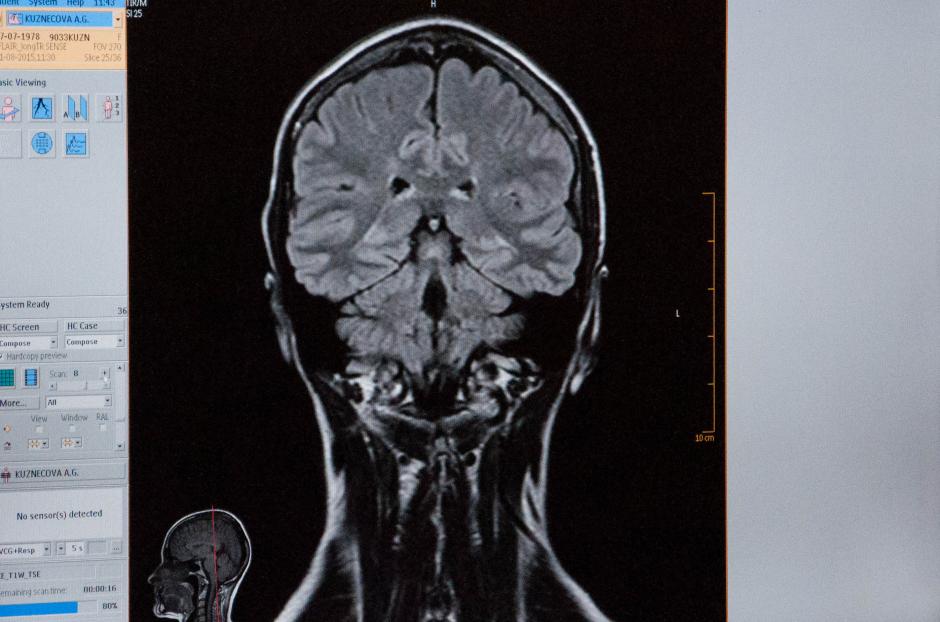

В Институте молекулярной и клеточной биологии и Международном томографическом центре СО РАН проводятся уникальные исследования по выявлению механизма и причин возникновения распространённого генетического заболевания, приводящего к умственной отсталости человека — синдрома ломкой Х-хромосомы (Мартина-Белл). Учёные Сибирского отделения РАН и Новосибирского государственного университета собираются наладить комплексный метод диагностики болезни, начиная с молекулярного уровня на культурах клеток и заканчивая анатомическим, для чего проводят томографический анализ изменений, происходящих в головном мозге пациентов.

МРТ-исследование дополнит картину заболевания |

Такой метод — наиболее информативный |

| Медики готовят контрастное вещество | Пациент получает задания | Происходящие изменения демонстрирует томограмма |

Каждый снимок приближает к разгадке |